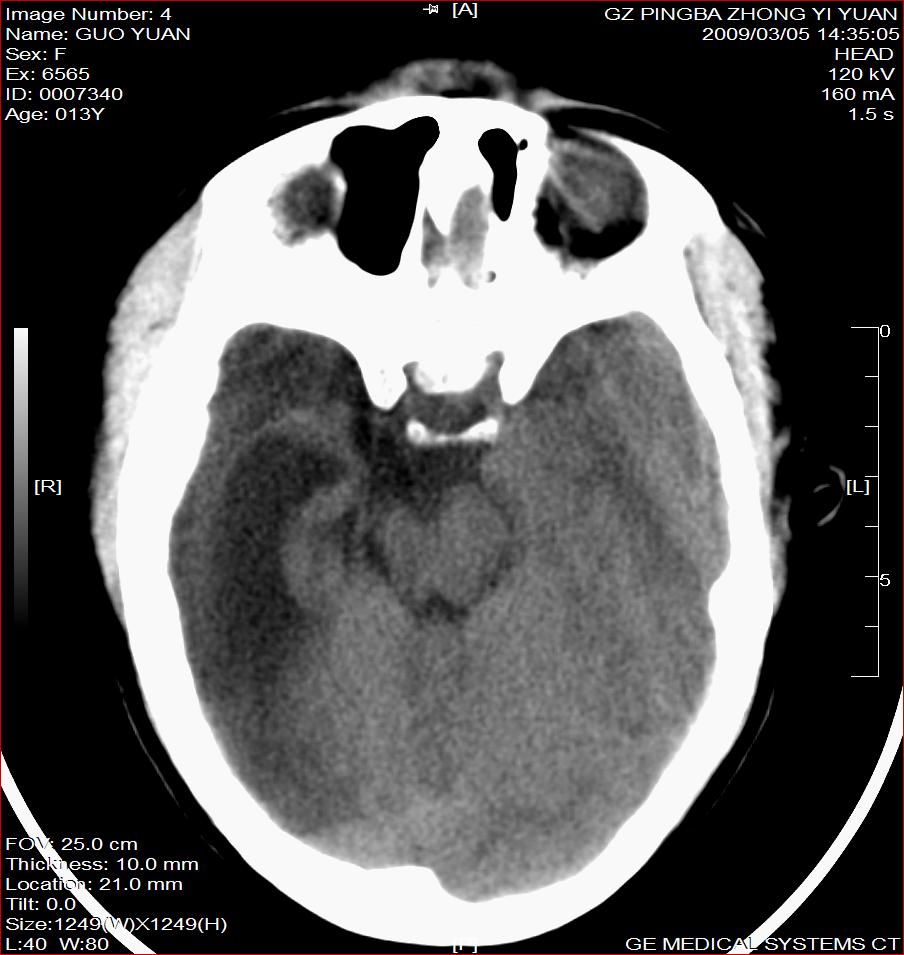

以下是引用杀毒软件在2009-3-6 17:32:00的发言:[br]右侧额颞顶部脑沟裂增宽,颞顶部楔形稍低密度影,侧脑室体部明显增宽,余脑实质内未见异常,中线结构居中。[br][br]考虑---右侧大脑半球发育不良并脑沟裂发育畸型可能性大

以下是引用随光逐影在2009-3-6 18:35:00的发言:[br]1)考虑右侧幕上半球发育不良并脑软化灶。2)双侧额部头皮软组织肿胀。